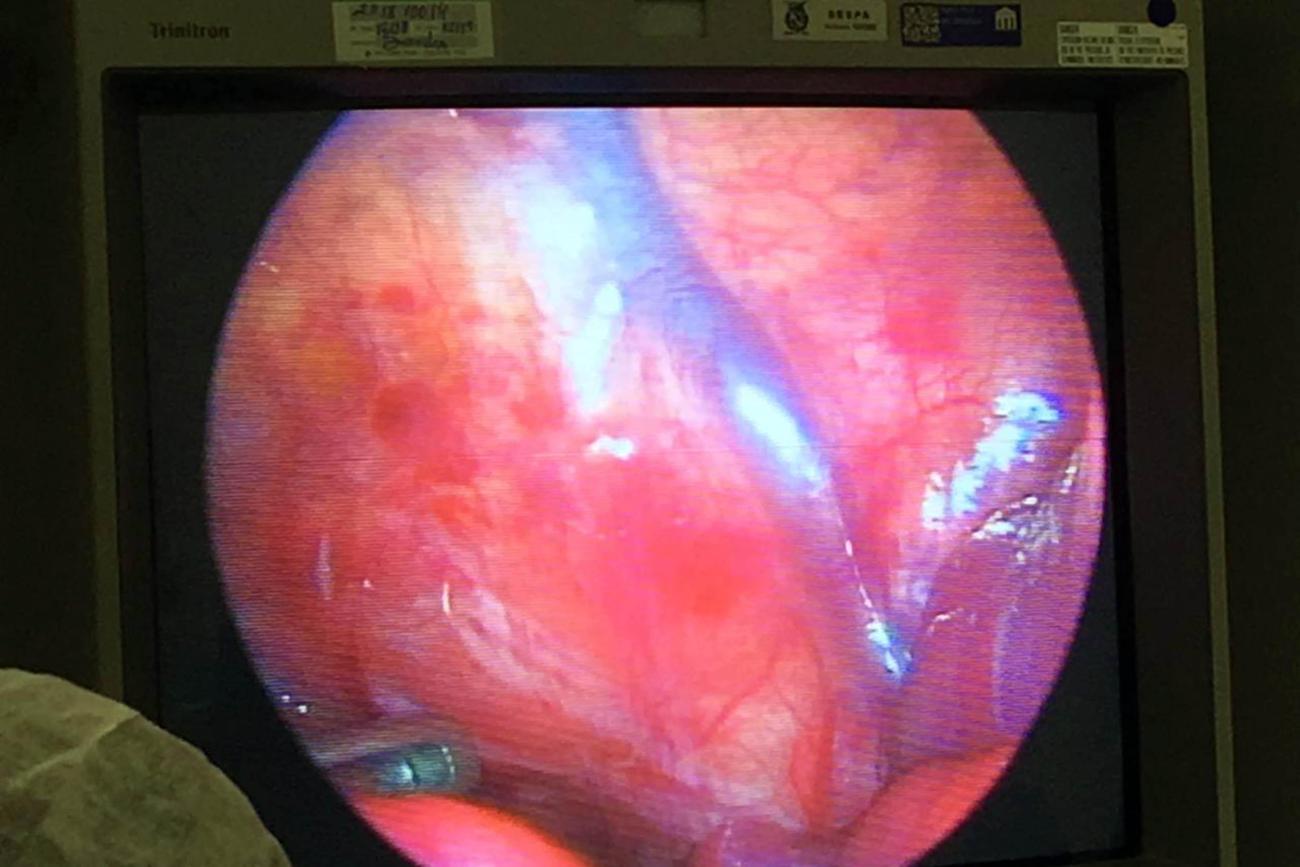

Já está em casa e se alimentando corretamente a bebê que passou pela cirurgia de videotoracoscopia (Cirurgia torácica videoassistida). Essa foi a primeira vez que a equipe médica de cirurgia pediátrica da Santa Casa realizou o procedimento. A intervenção cirúrgica foi necessária para realizar uma correção no esôfago do bebê, a criança tinha atresia de esôfago, uma má formação que o impede de se alimentar corretamente.

FOTO: ASCOM SANTA CASA

DATA: 05.02.2019

BELÉM - PARÁ